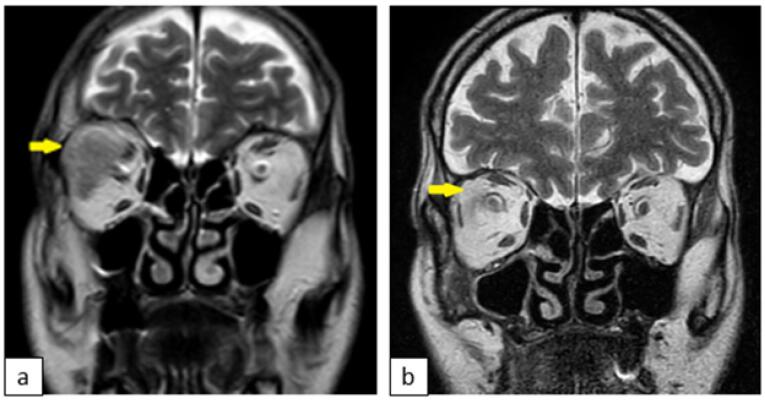

Chromophobe renal cell carcinoma (ChRCC) is a rare subtype of renal cell carcinoma (RCC). We present a case of a 61-year-old male with ChRCC who exhibited unusual metastasis to the retro-orbital area, a site rarely affected by RCC. The patient experienced diplopia and proptosis, prompting treatment with sunitinib and palliative radiotherapy. Remarkably, rapid improvement in ocular symptoms was observed following radiotherapy. Despite this localized response, the patient's overall condition deteriorated, highlighting the aggressive nature of ChRCC. This case underscores the importance of considering ChRCC in metastatic presentations and the potential efficacy of local palliative interventions.